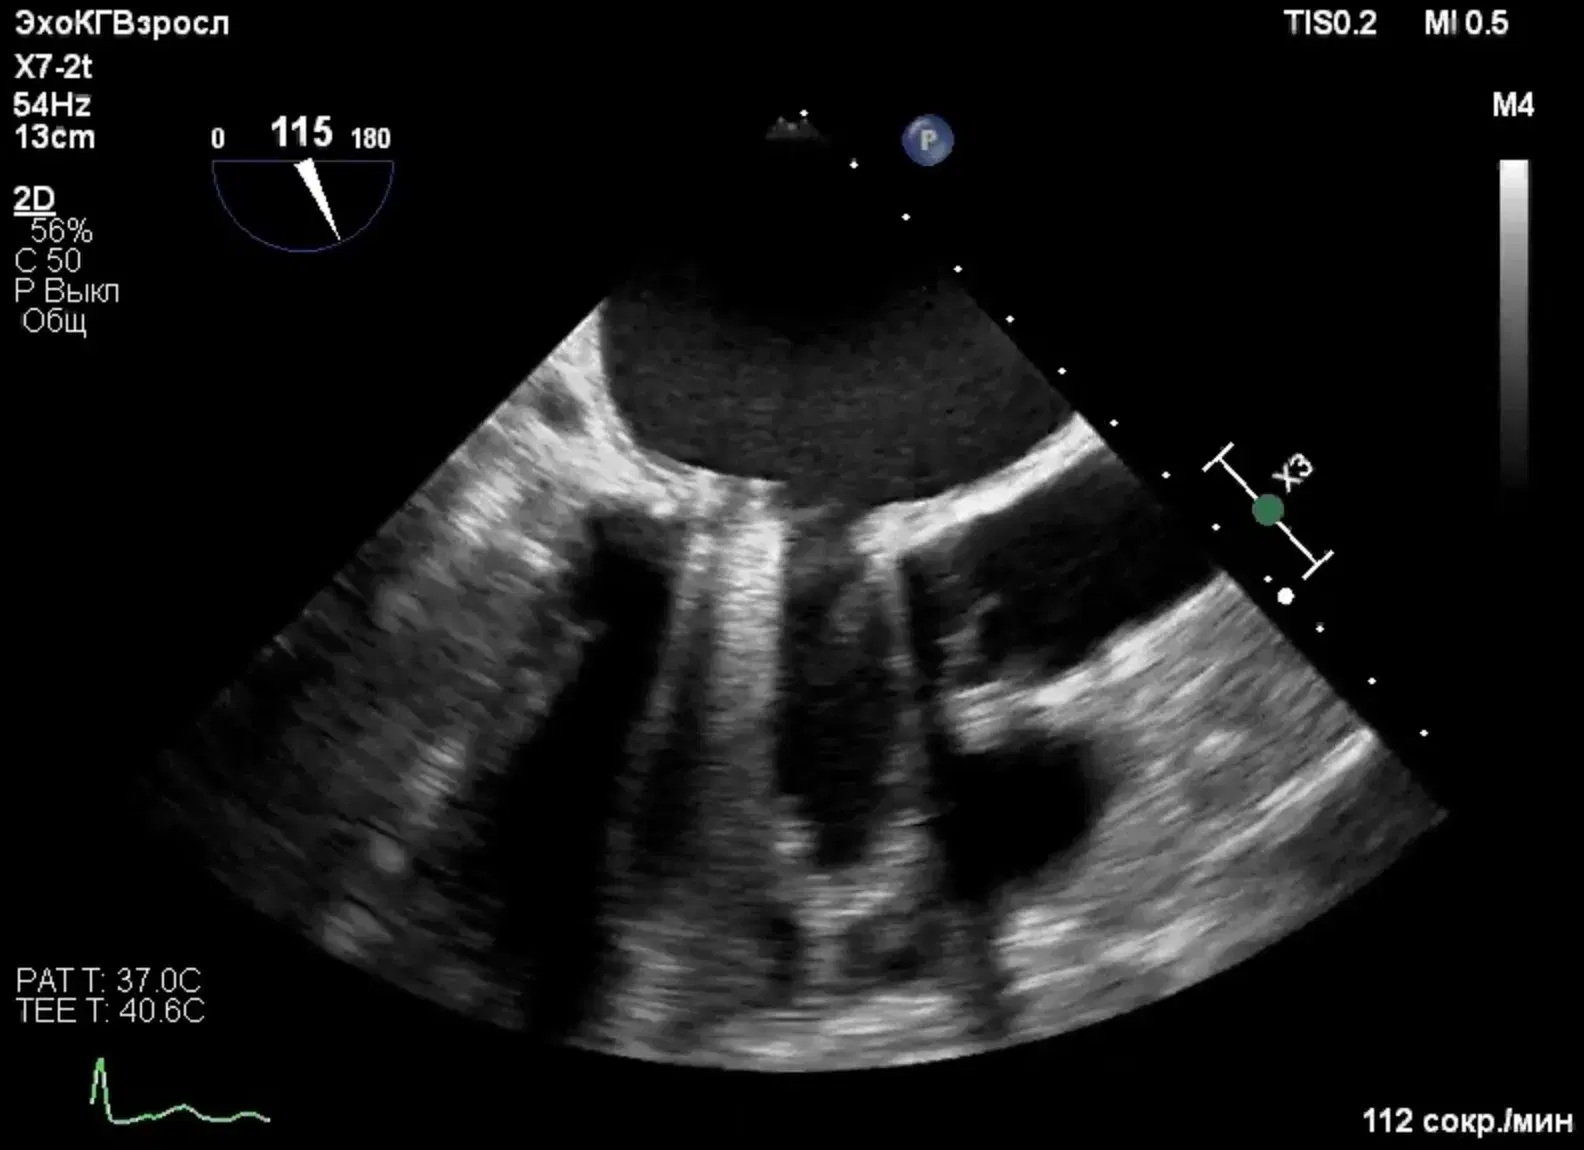

Learn to evaluate and diagnose infective endocarditis using echocardiography through real cases and develop diagnostic strategies for prosthetic valves.

Evaluate infective endocarditis using echocardiography

Analyze the different manifestations of infective endocarditis

Develop tips and tricks for diagnosing infective endocarditis in prosthetic valves